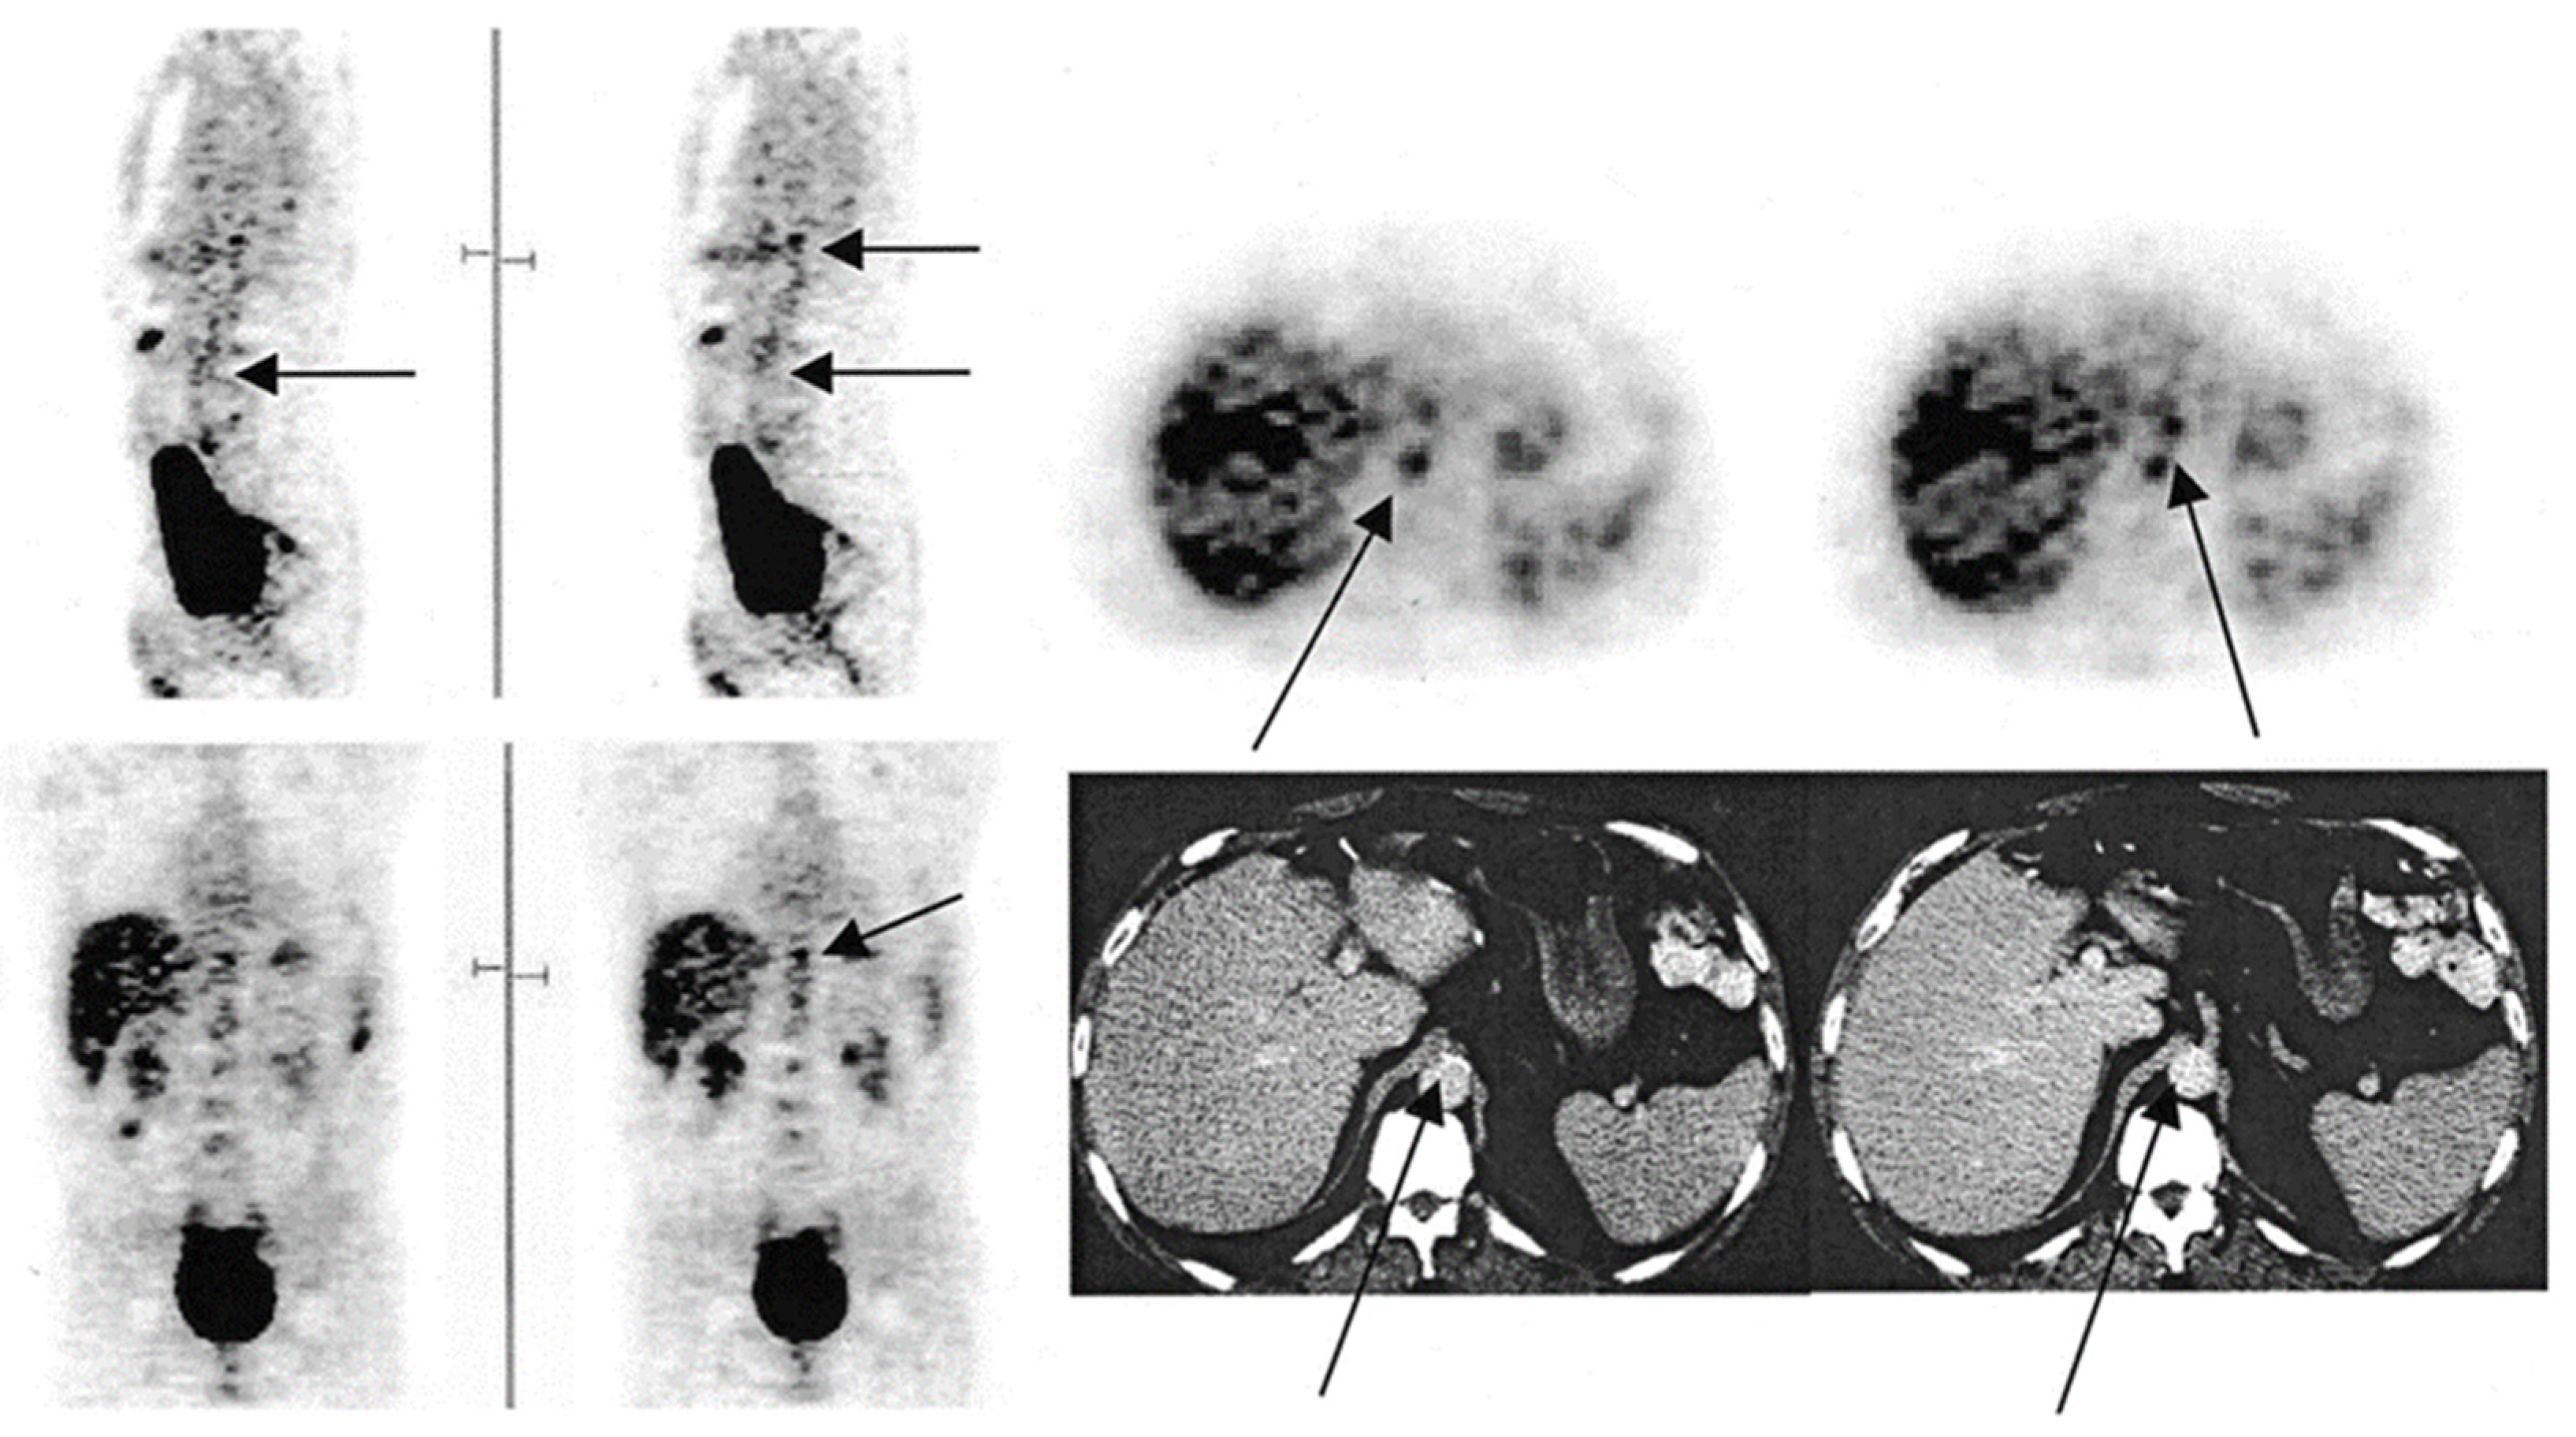

Figure 1.

FDG-PET images illustrating the foci of FDG uptake along the aorta. In the sagittal view, the arrow in the left image indicates the abdominal aorta, while the top arrow on the right points to the budding superior mesenteric artery. In the transverse view, the bottom and top arrows indicate the abdominal aorta and budding superior mesenteric artery, respectively. In the coronal view, the arrow points to the budding mesenteric artery. In the CT image, the left arrow points to calcification along the abdominal aorta, while the right indicates to the budding superior mesenteric artery (from Yun et al. [23] with permission).